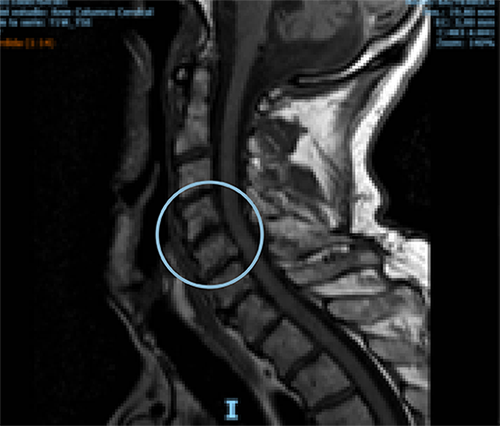

Comparative MRI of cervical spine pre- and one-year post-treatment in a 70-year-old man diagnosed with osteoarthritis of the cervical spine. The red arrow shows the remodeling of the affected disc.

AFTER